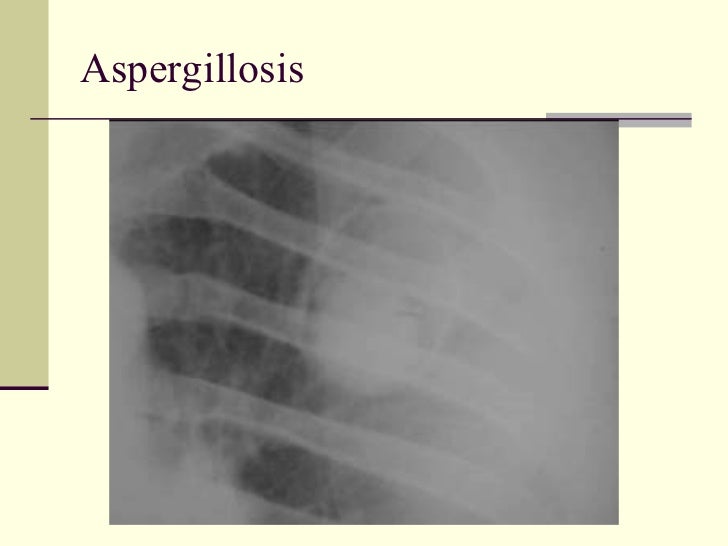

63. 71. <ul><li>Cavities Containing Masses </li></ul><ul><li>1. Aspergillosis </li></ul><ul><li>2. Cavitating bronchogenic ca </li></ul><ul><li>3 Tuberculosis </li></ul><ul><li>4 Hydatid cyst </li></ul>

64. 72. Aspergillosis